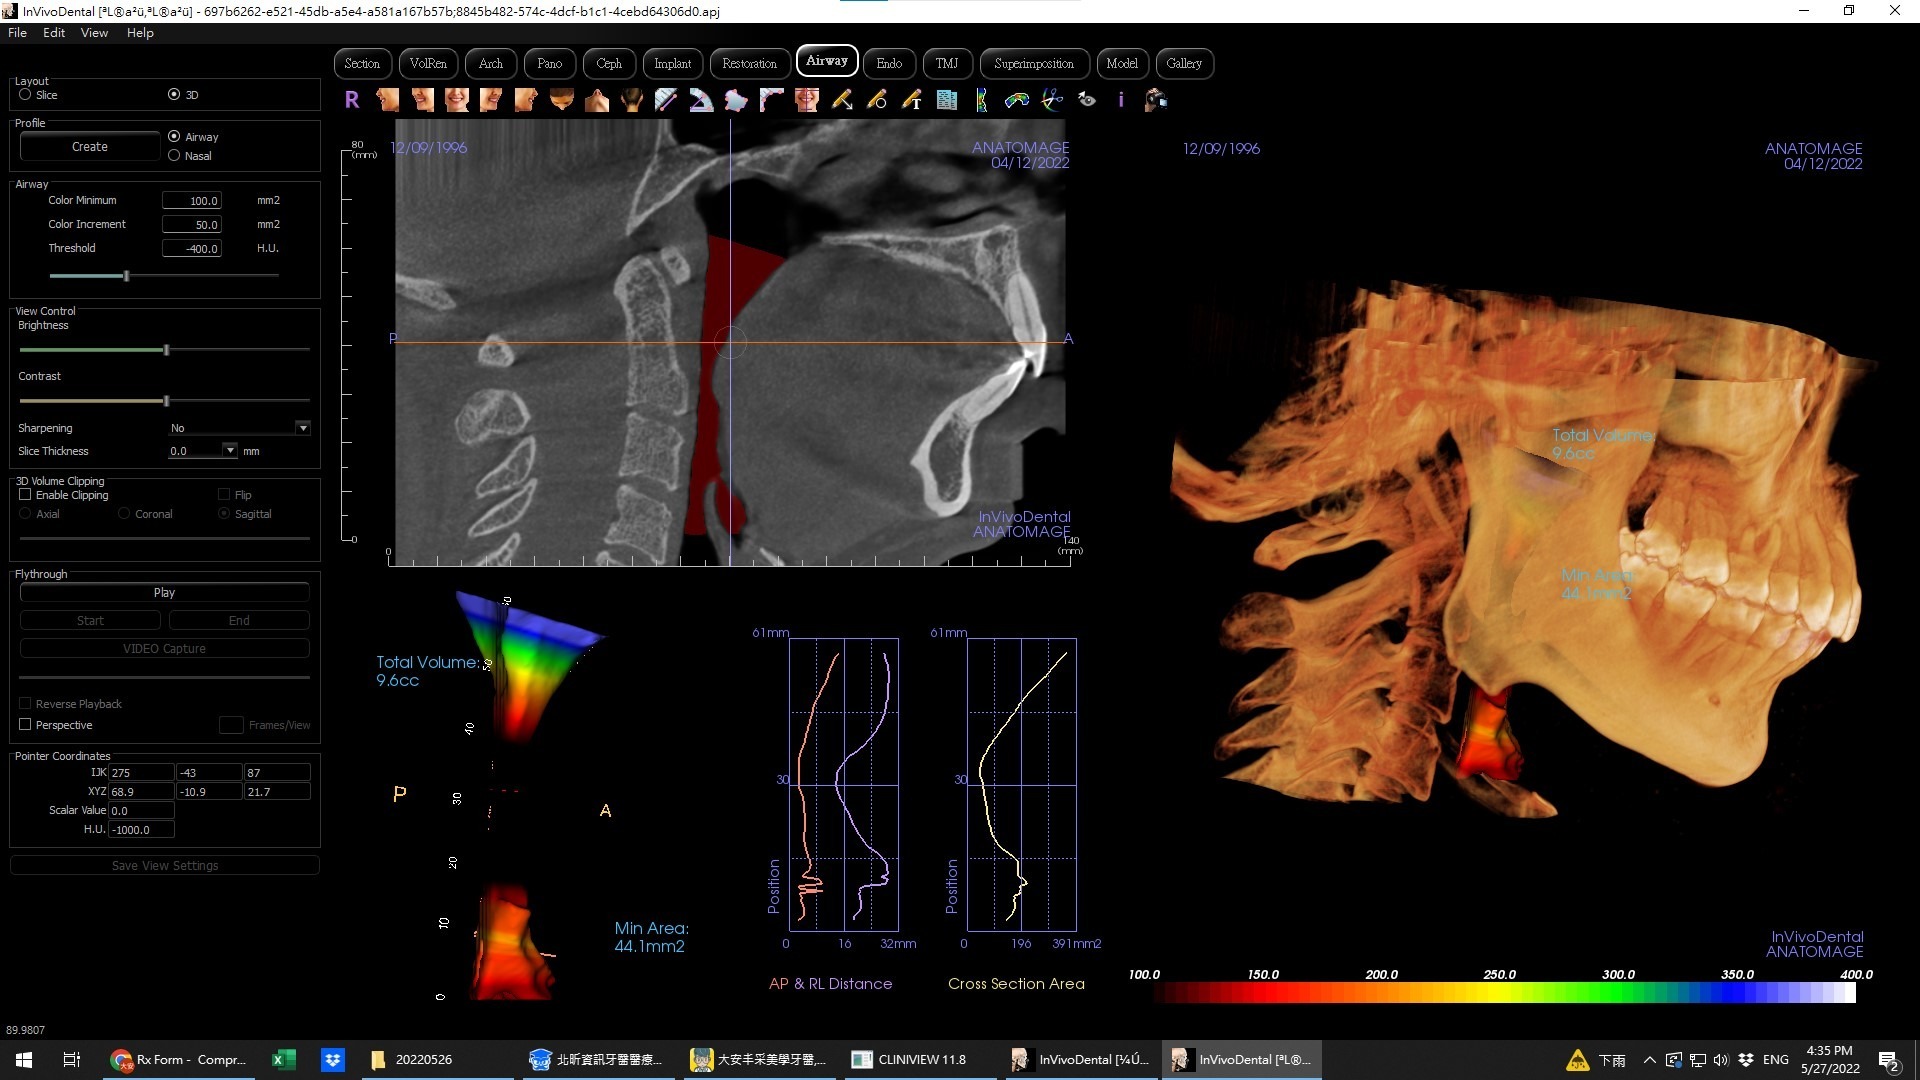

深入診斷烏龜頸 「呼吸道電腦斷層」是關鍵!

為了更精準地找出烏龜頸背後隱藏的呼吸道問題,牙醫師常會建議進行呼吸道電腦斷層檢查(Airway CT)。這項先進的影像工具,能無創、快速且安全的幫你評估氣道狹窄的位置與程度,確認下顎骨、顱底、頸椎的解剖結構,並作為睡眠呼吸中止症(OSA)等疾病的評估與追蹤依據。如果你長期受肩頸痠痛困擾,且一般復健效果不彰,或有打呼、白天嗜睡等問題,這項檢查能幫助你從根源找到答案!